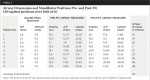

All patients showed an increase in oropharynx volume after using the step back technique. Baseline airway volumes averaged 13.51 cubic centimeters (SD = 6.08). After the mandibular position adjustment using the SBT protocol with the AMPG, airway volumes increased to 19.97 cubic centimeters (SD = 8.81), a 50% increase. This increase was significant, based on a paired sample t-test, t (8) = -4.27, p = 0.003. Pearson correlations showed that vertical and A-P adjustments were unrelated, at r = -0.20, n.s. (n.s. = non-significant). Neither the A-P (r = 0.19, n.s.) nor the vertical (r = 0.15, n.s.) adjustment alone related to significant airway change.

Table 2 summarizes the results of each patient’s adjusted mandibular position along with the pre- and post-test airway volume. Figure 2 and Figure 3 show pre- and post-test CBCT scans of patient No. 5, and Figure 4 shows each patient’s A-P and vertical setting with resulting area airway opening and volumetric increases.

Pre- and post-test results indicate at least three conclusions. First, each person’s mandibular adjustment needs are unique and require an individual approach to adjusting their mandible for oropharynx patency. As shown in Table 2, A-P final measurements varied from -3.5 mm to +4 mm and vertical measurements varied from 6 mm to 8.5 mm. The adjustment to the A-P does not appear to covary with adjustment to the vertical (r = -0.20, n.s.). As shown in Table 2, some airways opened with the most adjustment to A-P, some required most adjustment to vertical, and some required both. The absence of a correlation between adjustment size and change in cross-sectional airway was also found by Gale et al.13 If confirmed with a larger sample size, this indicates that personal adjustment for airway openings needs to be accomplished without any a priori set of adjustments as the goal.

Second, in this study, adjusting the mandible in the vertical plane was important in achieving airway improvement for most patients. Past research and practice has yielded a variety of recommendations regarding vertical adjustment as opposed to only A-P adjustments. Some have only manipulated the A-P13,14 while others have manipulated both.15,16 Based on research findings, some recommend manipulating only the A-P16,17; others recommend manipulating both A-P and vertical.18 In the current study, some patients needed minimal vertical adjustment and others needed both vertical and A-P. Thus, the authors recommend considering both dimensions when fitting appliances.